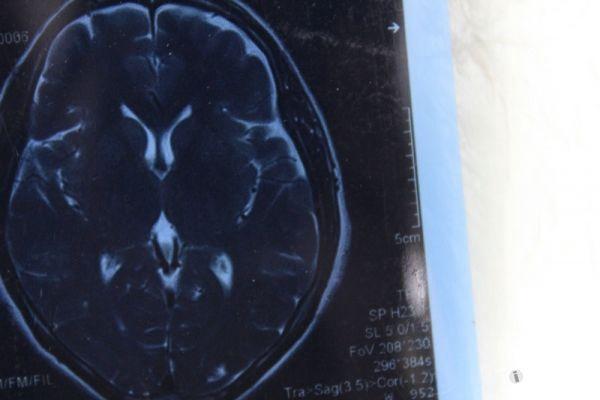

脑部占位病变CT,MRI图片,请帮忙诊断

最近感图样,无其它脑病病史

考虑脑膜瘤!!

磁共振没有平扫,增强矢状位没找到病灶。像脑膜瘤。

图片不是很清楚,应该是脑膜瘤!